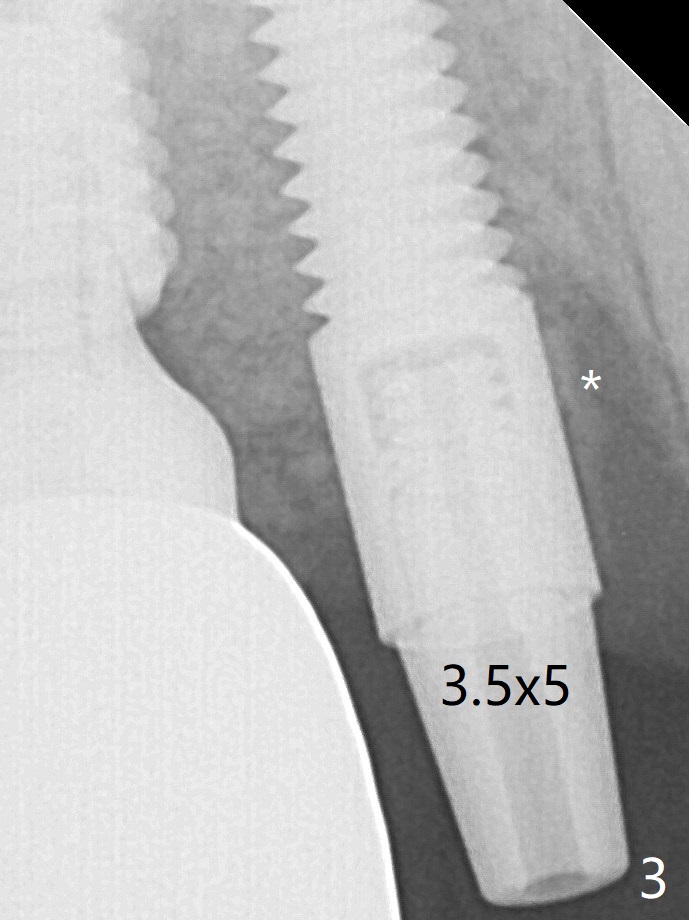

A 4x14 mm dummy implant is placed free hand (Fig.1). Following initial placement of a final 4x17 mm implant and bone graft (Fig.2 *), the crown and abutment of #3 and the guide are reseated for correct implant trajectory. The guide has to be removed for final depth control of the tissue-level implant. More bone graft is inserted mesial of #4 implant with a 3.5x5 mm abutment (Fig.3 *). The implant at # 4 seem to have osteointegrated, especially mesial, nearly 5.5 months postop (Fig.7,8).